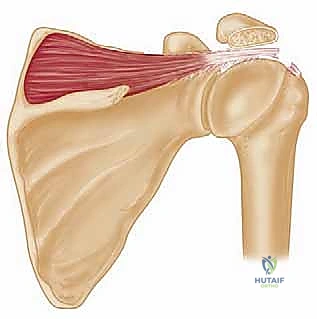

The Latissimus Dorsi Muscle and Tendon:

The latissimus dorsi is a broad, powerful muscle with a vast origin from the aponeurosis of spinous processes T7 through L5, the sacrum, the iliac wing, ribs 9 through 12, and the inferior border of the scapula. Its fibers twist a remarkable 180 degrees from origin to insertion. This anatomical peculiarity allows the muscle, originating posteriorly, to insert immediately anterior to the teres major tendon on the proximal humerus. Its tendon averages 3.1 cm wide and 8.4 cm long at its insertion. Critically, the latissimus dorsi humeral insertion never extends more distal along the humeral shaft than that of the teres major. This distinction is vital during our dissection.

The Rotator Cuff and its Footprint:

The supraspinatus and infraspinatus muscle-tendon units originate from their respective fossae and become confluent, inserting as a common tendon on the greater tuberosity of the humerus, immediately lateral to the humeral head articular margin. Their combined footprint area averages 4.02 cm². The supraspinatus insertion averages 1.27 cm medial to lateral and 1.63 cm anterior to posterior, while the infraspinatus insertion averages 1.34 cm medial to lateral and 1.64 cm anterior to posterior. The deepest fibers of these tendons are intimately interwoven with the joint capsule, forming a functional unit. Consequently, tears here lead to direct communication between the glenohumeral and subacromial spaces.